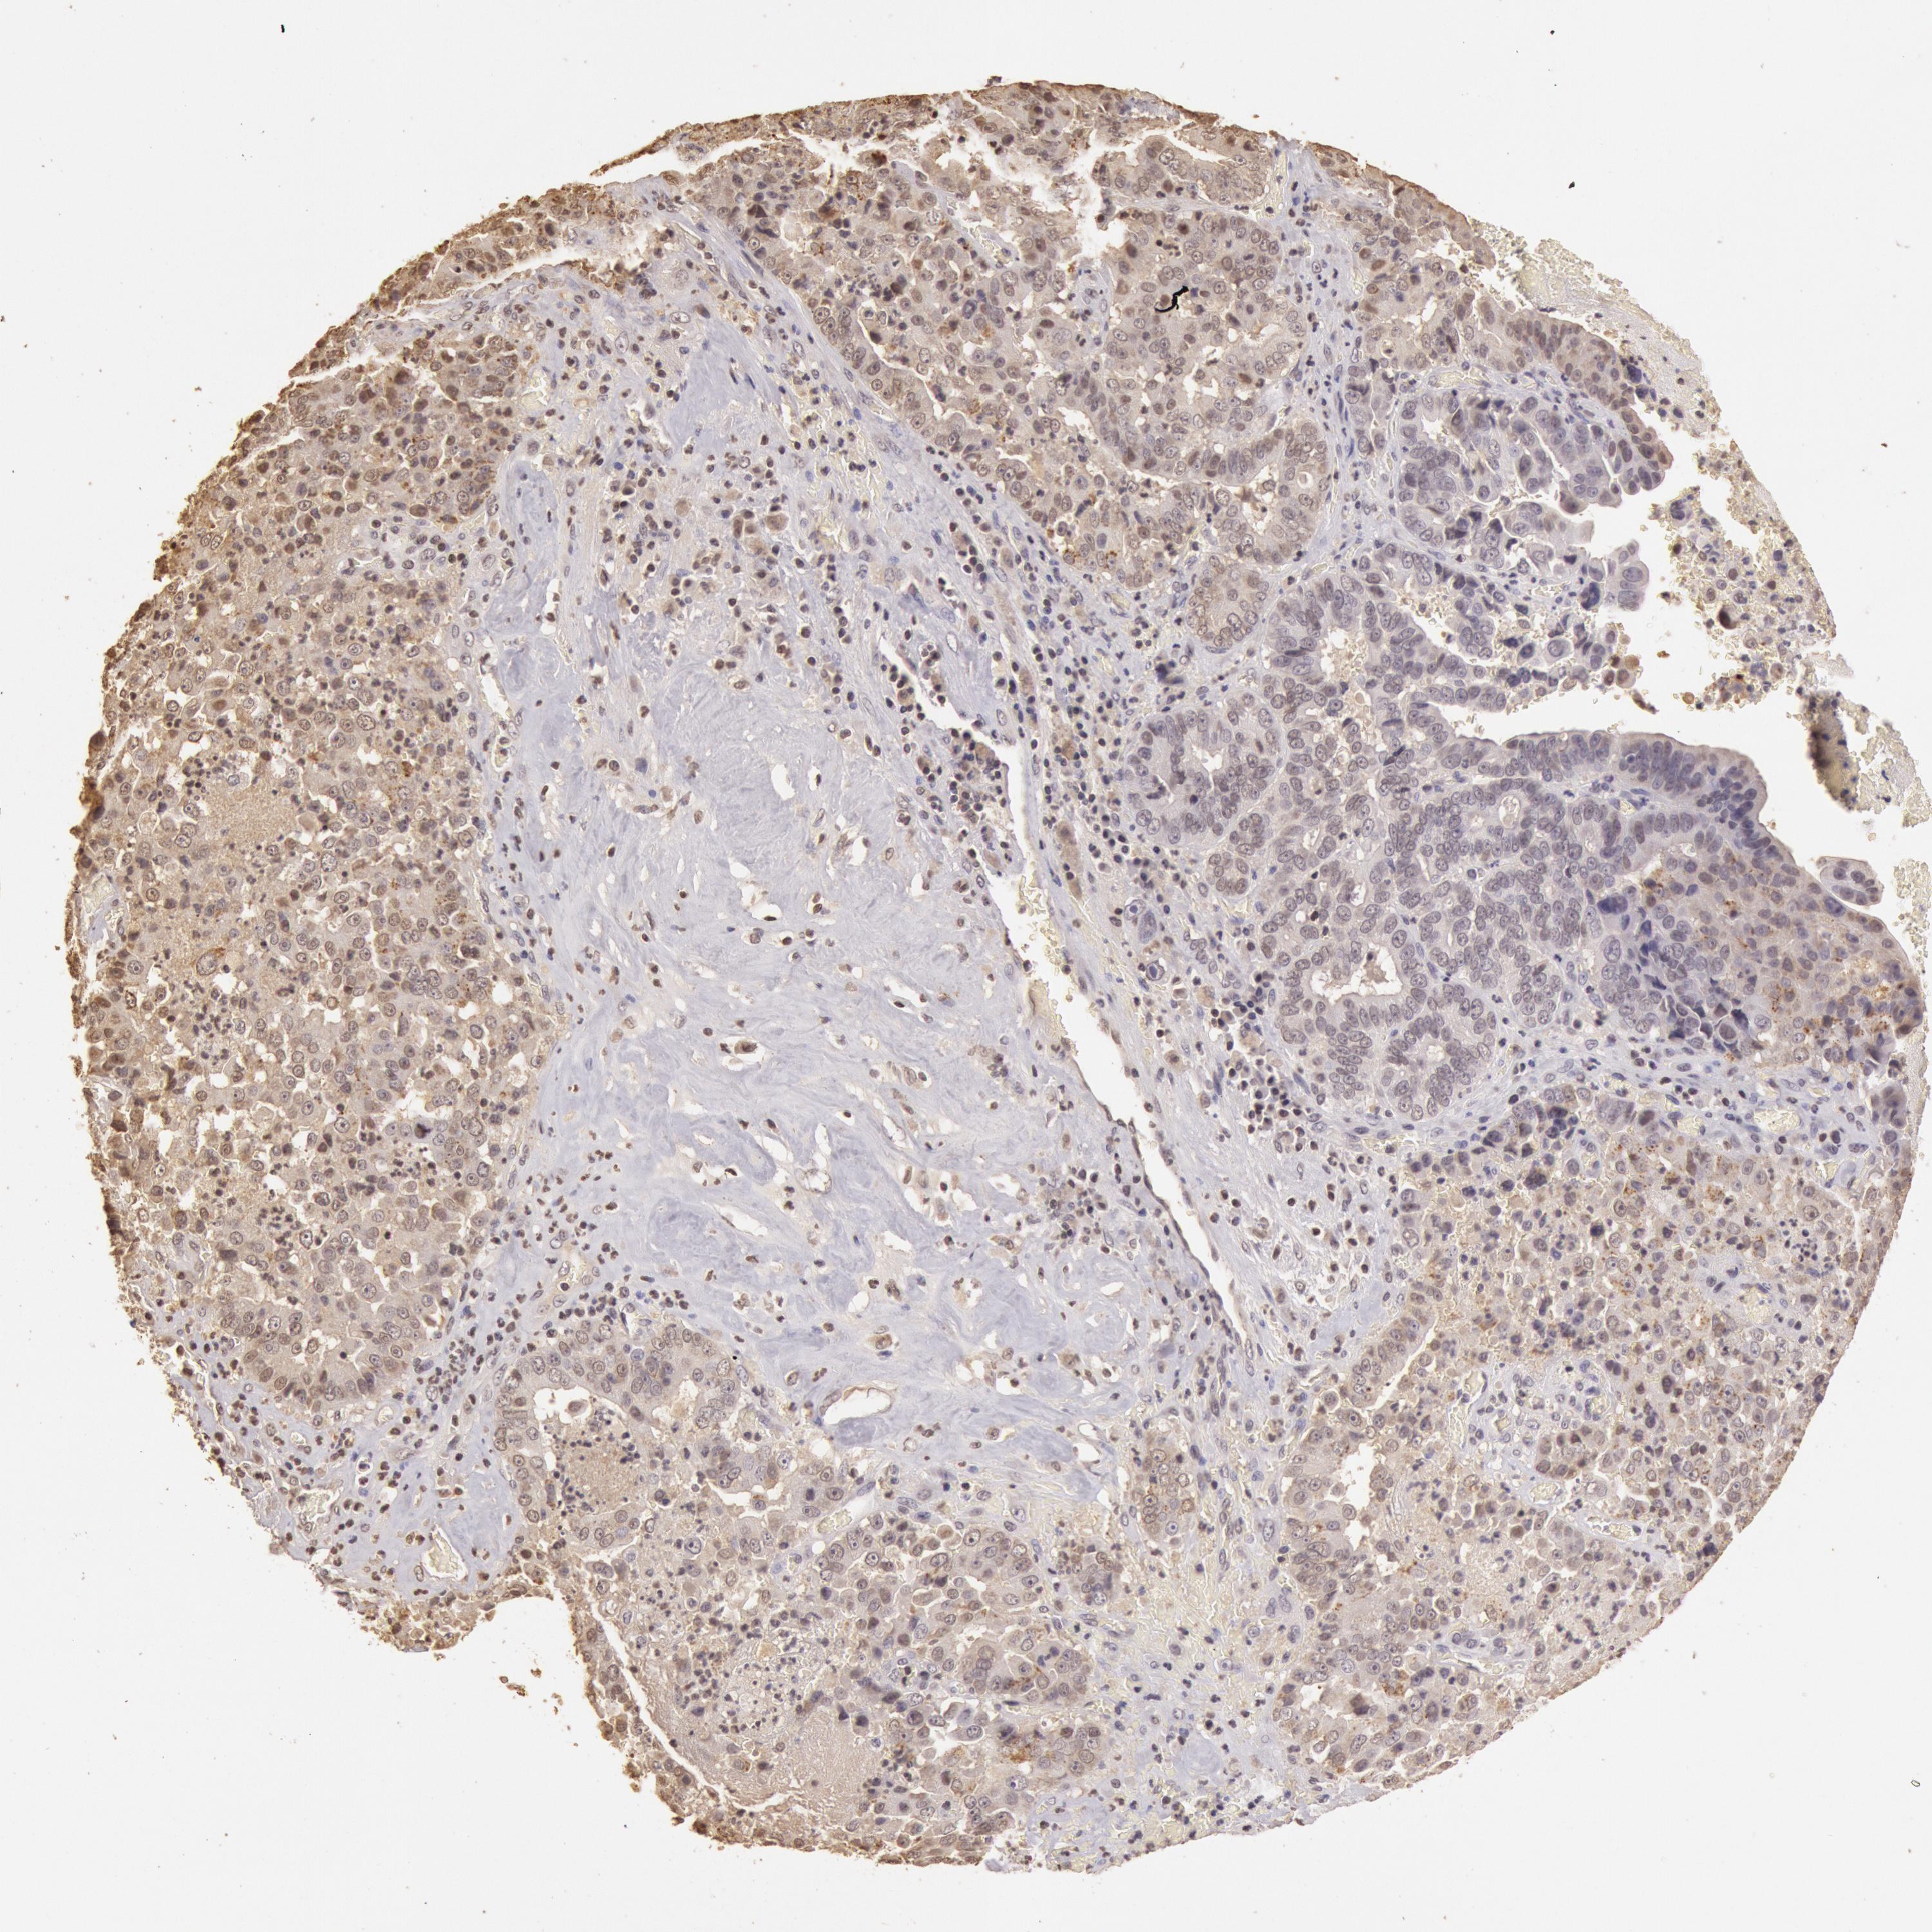

LIVER CANCER - Protein expressioni

A mouse-over function shows sample information and annotation data. Click on an image to view it in a full screen mode. Samples can be filtered based on level of antibody staining by selecting one or several of the following categories: high, medium, low and not detected. The assay and annotation is described here.

Note that samples used for immunohistochemistry by the Human Protein Atlas do not correspond to samples in the TCGA dataset.

Antibody stainingi

Antibody staining in the annotated cell types in the current human tissue is reported as not detected, low, medium, or high, based on conventional immunohistochemistry profiling in selected tissues. This score is based on the combination of the staining intensity and fraction of stained cells.

Each image is clickable and will lead to virtual microscopy that enables deeper exploration of all samples and also displays staining intensity scores, fraction scores and subcellular localization as well as patient and tissue information for each sample.

Antibody HPA001401

Antibody CAB008670

Staining

High

Medium

Low

Not detected

Intensity

Strong

Moderate

Weak

Negative

Quantity

>75%

75%-25%

<25%

None

Location

Nuclear

Cytoplasmic/membranous

Cytoplasmic/membranous,nuclear

Carcinoma, Hepatocellular, NOS

Cholangiocarcinoma